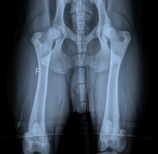

Gezondheid en Welzijn

We zijn trots om te kunnen zeggen dat Louie volledig gecontroleerd is op heupdysplasie, een veelvoorkomend probleem bij veel hondenrassen, en dat hij helemaal gezond is. Dit is cruciaal voor ons, omdat we willen garanderen dat Louie's nakomelingen gezond en sterk zijn.